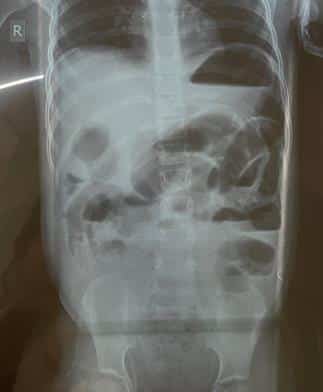

Upon blood investigations, mean corpuscular volume (MCV), mean corpuscular hemoglobin (MCH), and mean corpuscular hemoglobin concentration (MCHC) were increased. Total WBC count was within normal limits (9,600 μL), and lymphocytes were decreased. Serum sodium and chloride were decreased, whereas high-sensitivity CRP (HS-CRP) was increased (more than 5 mg/dl; normal: 0.5-1.5). An X-ray of the erect abdomen was taken in standing posture, which showed multiple air fluid levels, fundal air in the stomach, and no air under the diaphragm. This indicated that an obstruction might be present past the level of the small intestine. The X-ray (figure 1) shows no evidence of any air under the diaphragm, and multiple air-fluid levels are noted within the visualized small bowel loops. Fundal air in the stomach is present.

Figure 1: X-ray of erect abdomen